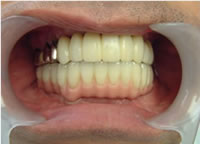

治療完了

平成21年1月29日

(治療期間:1年7ヶ月)

57歳 女性

治療後

インプラント21本 すべてジルコニア冠